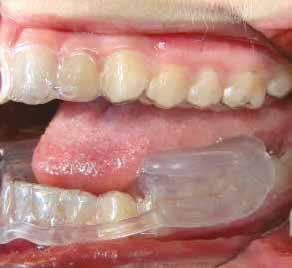

Az Essix retainerek, az egy fogívre kiterjedő mélyhúzott sínek, valamint a felső és alsó frontfogakra orálisan ragasztott fix retainerek mellett, a harapás sagittális rögzítésében elengedhetetlen szerepe van az ún. Pitts Izom Tréning Splint-nek, amelybe a páciens élharapásban összeharap, így az megakadályozza az alsó fogsor visszamozdulását a disztálharapásos helyzetbe (13. kép)

26 e-Journal ORTHODONTIA